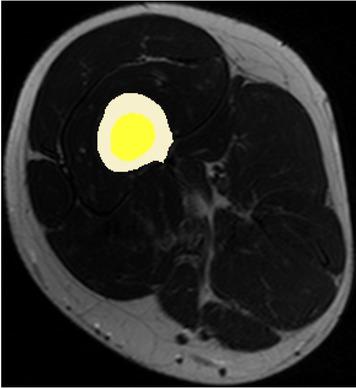

Fig. 3